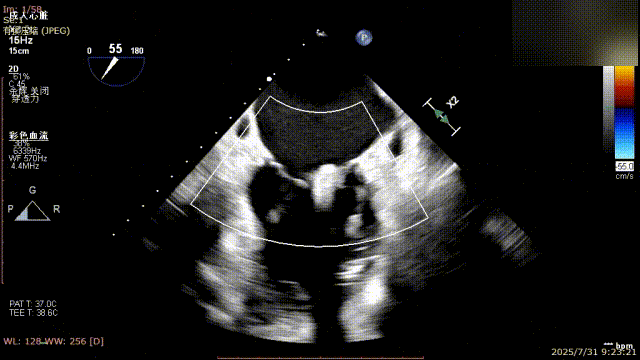

手术过程中,麻醉与围术期医学科副主任医师马金本确保麻醉过程平稳。心脏大血管外科主治医师董明亮穿刺股静脉置入血管鞘,并在心脏超声科梁皓主任及段福建教授TEE引导下,顺利穿刺房间隔,房间隔穿刺高度4.9cm。随后,在王安彪主任以及刘洋教授指导、心脏超声科梁皓主任TEE引导下,董明亮医师沿输送系统将延展呈“一字型”状态的国产夹合器送至左房,缓慢关闭夹合器并进行弹道测试。调整夹合器位置和方向后,董明亮医师再次将夹合器延展呈“一字型”完成跨瓣,避免发生腱索缠绕,成功捕获瓣叶后关闭夹合器,二尖瓣反流显著下降。夹合器完全解离后,超声示二尖瓣反流程度显著下降,残余反流0,平均跨瓣压差1mmHg,手术圆满成功。

解离后瓣叶及反流